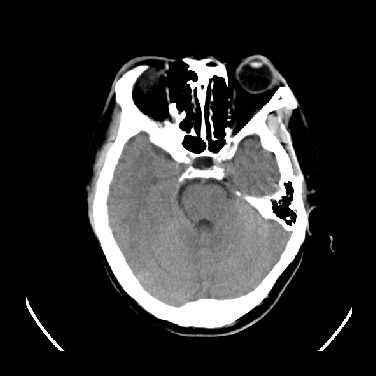

标题: CT16999:男,45岁,左侧肢体乏力1周。请会诊 [打印本页]

男,45岁,左侧肢体乏力1周。ex:胸片示:两肺团块状、斑片状密度增高影,其内可见小空洞。支纤镜、经皮肺穿示:干酪样物。

考虑右侧顶叶脑脓肿形成。

考虑右侧顶叶脑脓肿形成

右侧顶叶脑脓肿!支持!

考虑右侧顶叶脑脓肿(结核性?)。